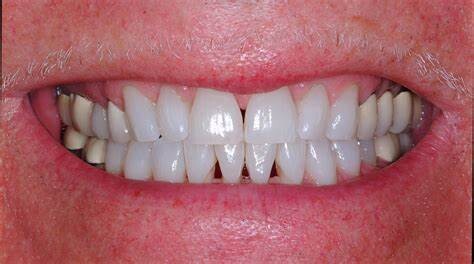

Have you lost gum from between your teeth? If you look at any magazine photo or advertisement you will see cosmetically beautiful smiles with uniform, straight teeth. The smiles you see in these magazines do not have gaps or spaces. If you have tiny triangles between two or more of your teeth, you may feel self conscious about their appearance.

Unfortunately, lost gum between teeth can indicate that the tissue is not as healthy and strong as it should be. Often, gum treatment is needed before cosmetic alterations can be made to fill these spaces. Good oral hygiene is important for your teeth and gums and patients are encouraged to improve how they brush and floss. Once your gums have been treated and are healthy, treatment for the dark spaces can be done. You can say goodbye to these black spaces in your smile through one of three treatment options.

What causes lost gum from between teeth?

In simple terms, space opens between teeth is caused by trauma, receding gums, and gum disease. From a distance, those spaces look like there is food is caught between your teeth. Upon professional inspection, those black spots can indicate a bigger dental problem. You may wish to fill spaces between the teeth for a more uniform appearance.